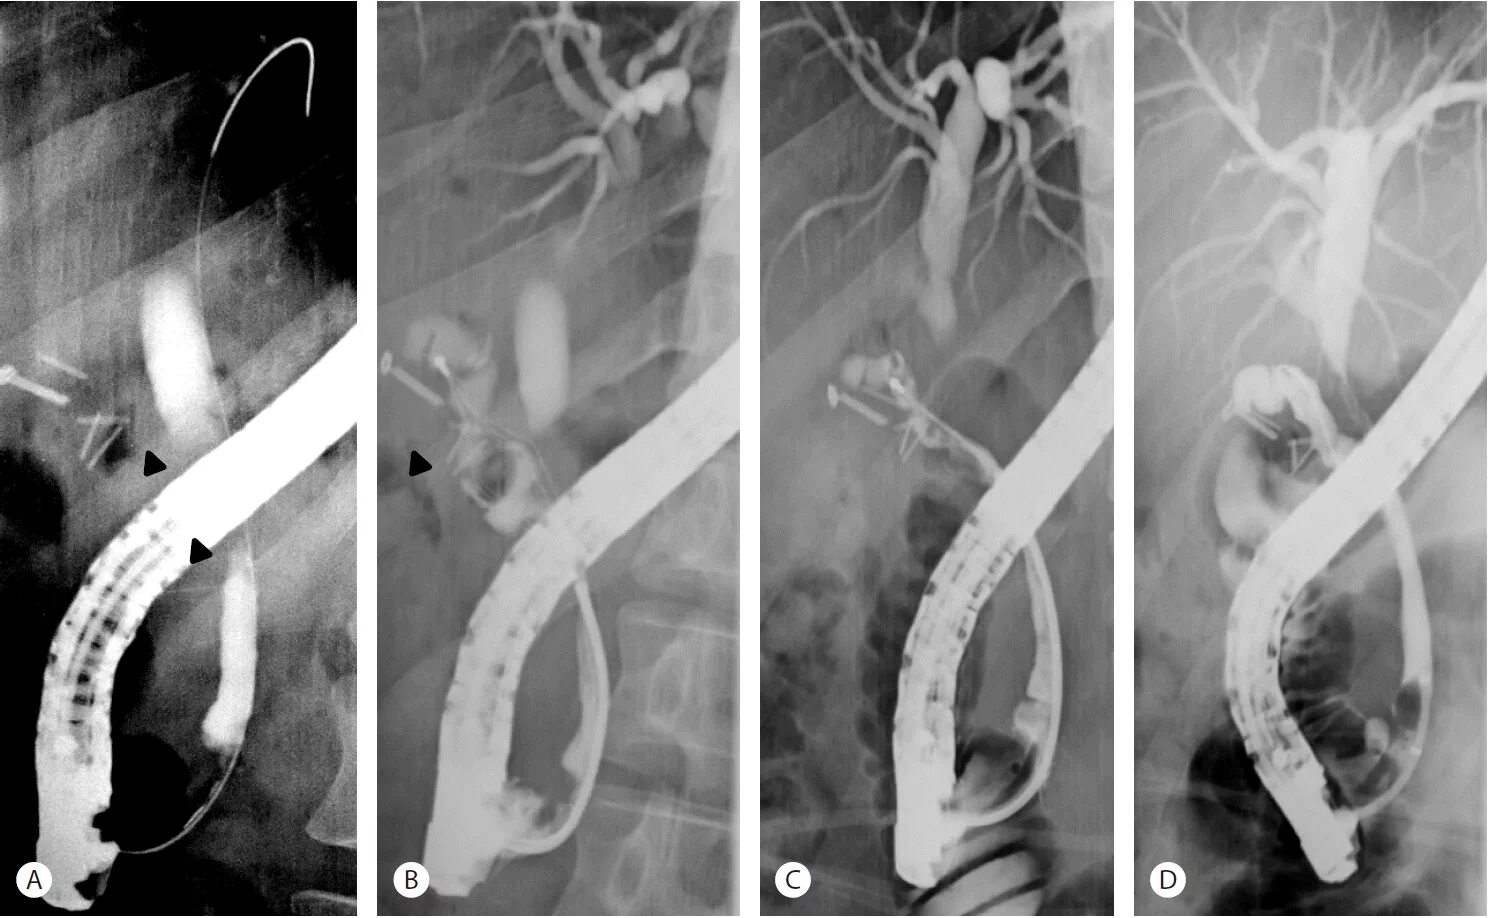

Стенты мрт